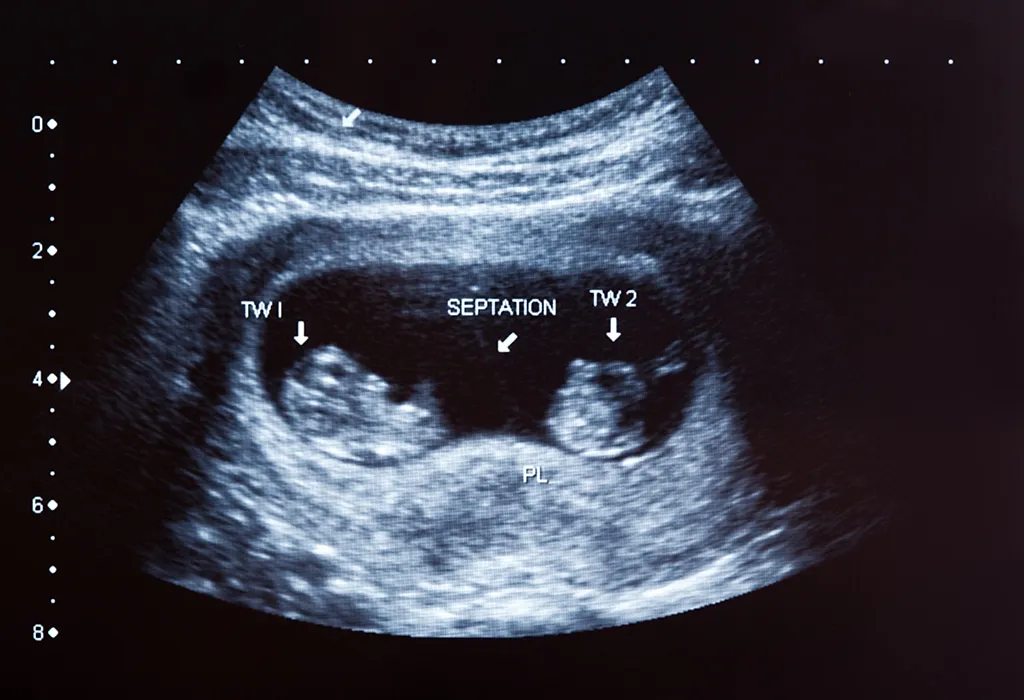

एचसीजी हे एक संप्रेरक आहे. गर्भधारणा झालेली आहे किंवा नाही हे ह्या संप्रेरकांमुळे समजते. एका बाळासह गरोदर असल्यास, एचसीजी पातळी 70 ते 750 mIU/ml (म्हणजे, मिलि इंटरनॅशनल युनिट्स प्रति मिलीलीटर, जे हार्मोन्स मोजण्यासाठी एक युनिट आहे) पर्यंत बदलते. जुळी बाळे असतील तर गरोदरपणाच्या सुरुवातीच्या काळात एचसीजी पातळी वाढलेली असू शकते. जुळ्या मुलांसाठी सामान्य एचसीजी पातळी एकल गर्भधारणेच्या तुलनेत 30% ते 50% जास्त असते – काहीवेळा सुमारे 200 ते 1750 mIU/ml अशीही दिसून येते.

शरीर एचसीजी तयार करत नाही. उलट पोटात वाढत असलेल्या बाळापासून एचसीजी तयार होते. प्रत्येक विकसनशील बाळ काही प्रमाणात एचसीजी तयार करते. त्यामुळे जुळी बाळे असल्यास हे प्रमाण दुप्पट होते. ही संप्रेरके एकत्रितपणे गर्भाशयाचे अस्तर घट्ट करण्यासाठी कार्य करतात. हे अस्तर गरोदरपणात बाळाला आधार देतात.

जुळी बाळे असल्यास, एचसीजीची पातळी लक्षणीयरीत्या वाढते. त्यामुळे रक्त आणि लघवीमध्ये एचसीजी चाचण्यांद्वारे शोधले जाते. दर 48 ते 72 तासांनी ही पातळी दुप्पट होते.